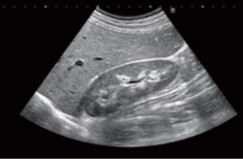

腹部超音波検査

腹部エコー検査では、胃カメラや大腸カメラでは観察できない、肝臓・胆のう・膵臓・腎臓・脾臓・膀胱・前立腺などの病気を見ることが出来ます。

また、胃や大腸も進行がんや潰瘍、強い炎症などはエコーでも指摘することができ、痛みや苦しさがなく、ベッドサイドですぐに出来るため非常に有効な検査です。